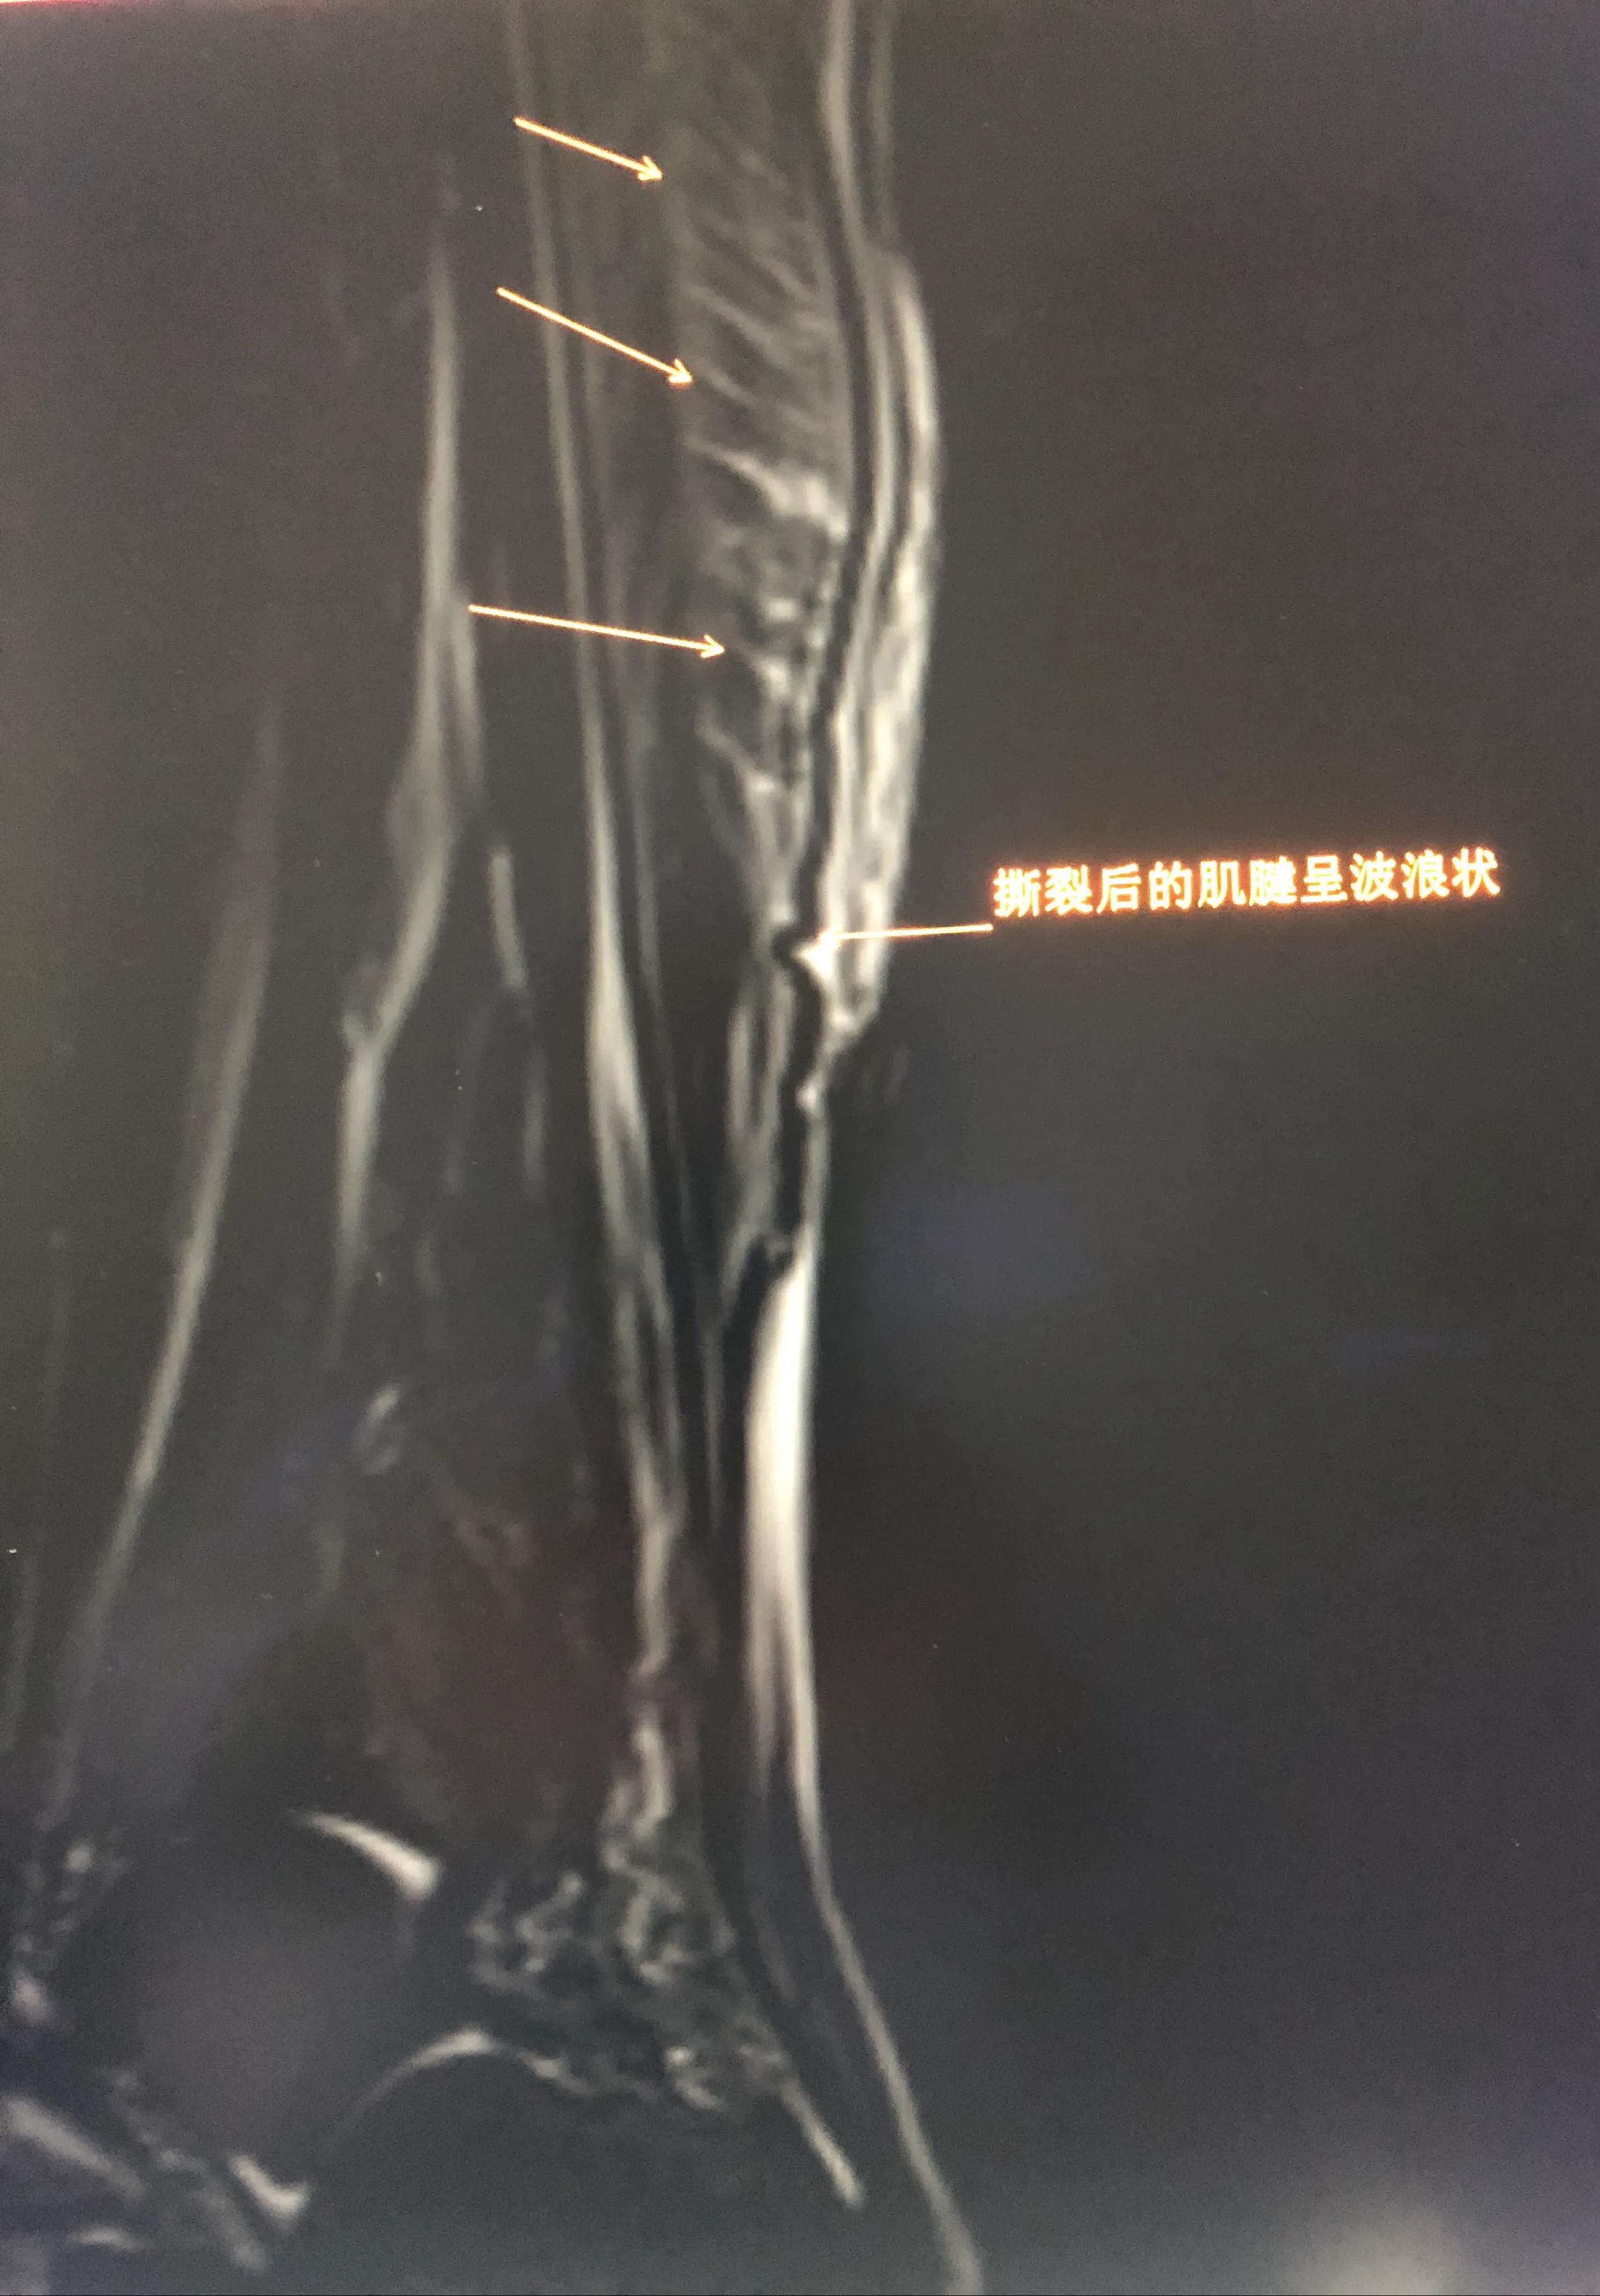

图3: 严重网球腿,不过已经过了急性期,渗出液大部分吸收。撕裂的肌肉呈木梳妆,断裂的肌腱呈波浪状。